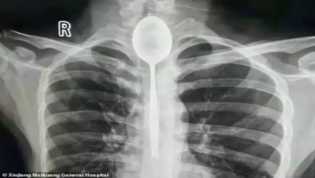

Pria Asal Tiongkok Biarkan Sendok di Kerongkongannya hingga Sulit Bernapas

Ahad, 28 Oktober 2018

- 22:07:10 WIB